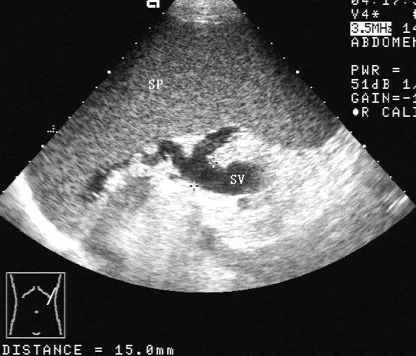

灰阶超声,脾肿大,显示肿大的脾脏(SP),内部回声均匀,长径为165mm。

灰阶超声,脾肿大,显示脾门处增宽的脾静脉(图1,SV),内径达15mm 。彩色多普勒,显示增宽的脾静脉彩色血流(图2)。

SP:脾脏     SV:脾静脉。